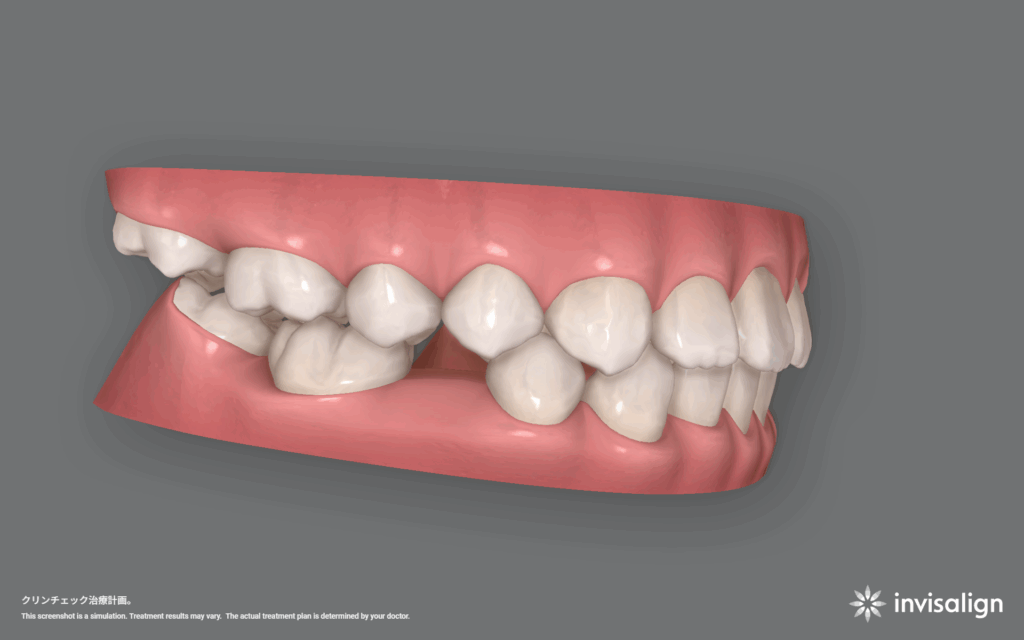

インビザライン矯正治療。57ステージ。治療費766,700円+調整料(初回)16,500円+調整料5,500円×回数+リテーナー55,000円。

1日20時間以上装着、1ステージ10日間。つまり570日、約19ヶ月、約1年7ヶ月の計画です。

今回の計画は、数段階に分けて治療をしていきます。1段階目は歯の位置関係をできるだけ整える。2段階目は先天欠損している部位の隙間をなくす。3段階目は全体的にはの位置を整える。ことにしました。結構時間がかかると思いますが、本人もお母さんも同意してくれたので治療を開始することになりました。